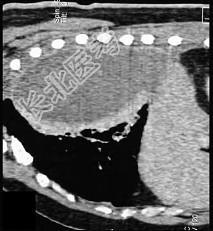

- 单项选择题男,59岁, 呼吸困难,胸痛, 有发热,请结合CT图像选择最可能的诊断 ( )

A、脓胸

B、肺脓肿

C、大叶性肺炎

D、肺囊虫病

E、肺癌